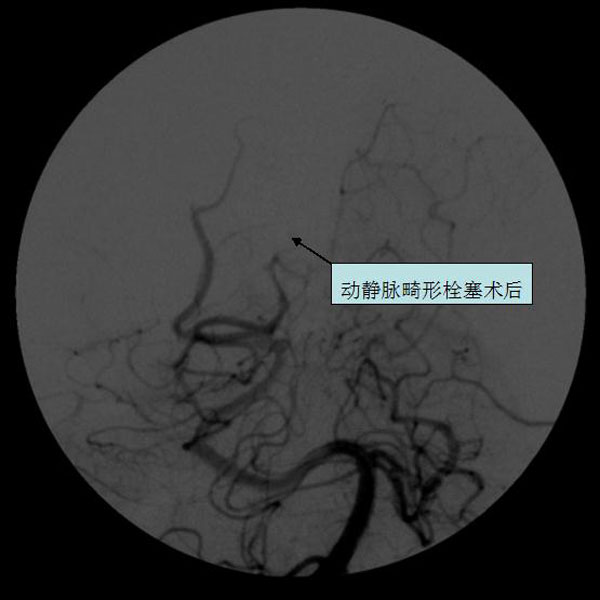

脑血管畸形介入栓塞

脑血管畸形栓塞术前

脑血管畸形栓塞术后